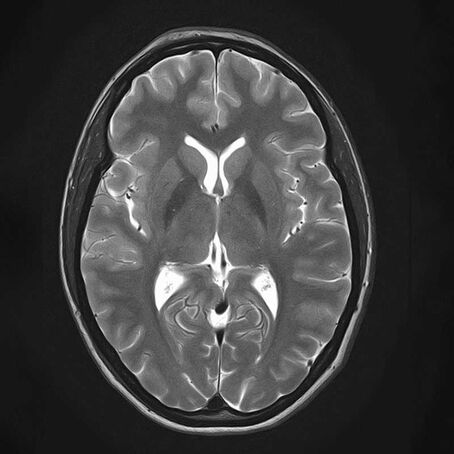

Magnetresonanztomographie (MRT, Kernspintomographie)

. Ein MRT-Scan eines menschlichen Gehirns, axialer Schnitt, zeigt Strukturen und Gewebe.

T2-gewichtete HR Sequenz des Neurokraniums

Die Magnetresonanztomographie stellt sämtliche Körperregionen überlagerungsfrei dar. Das Magnetfeld ist für den menschlichen Körper ungefährlich. Die Magnetresonanztomographie ist ambulant wegen des exzellenten Gewebekontrastes das wichtigste röntgenstrahlenfreie radiologische Diagnoseverfahren.